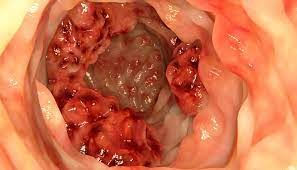

O câncer de intestino representa uma das principais causas de morte por câncer no Brasil, afetando anualmente milhares de famílias. Embora seja prevenível por meio de métodos diagnósticos acessíveis, como o teste de sangue oculto nas fezes e a colonoscopia, a doença permanece como grande desafio para o sistema de saúde brasileiro. Em resposta a essa realidade, a Sociedade Brasileira de Endoscopia Digestiva (SOBED), a Sociedade Brasileira de Coloproctologia (SBCP) e a Federação Brasileira de Gastroenterologia (FBG) se uniram novamente em torno da campanha nacional Março Azul, que em 2024 leva como lema Médico e paciente: uma parceria que salva vidas! Juntos na prevenção do câncer de intestino.

Prevenção – Atualmente, cerca de 85% dos casos de câncer de intestino são diagnosticados em fase avançada, o que aumenta os custos com o atendimento de saúde – cirurgias, quimioterapia, radioterapia – e diminui as chances de cura para um dos tumores malignos mais frequentes e fatais no País. “Evitar a doença e, principalmente, aumentar a possibilidade de cura e de sobrevida de seus pacientes exigem diagnóstico e tratamento precoces dessa doença, com impacto positivo não apenas pela preservação de vidas, como também pela redução de custos do sistema de saúde”, destaca Marcelo Averbach, presidente do Núcleo de ações sociais da SOBED, presidente da ONG Zoé e coordenador da campanha nacional.